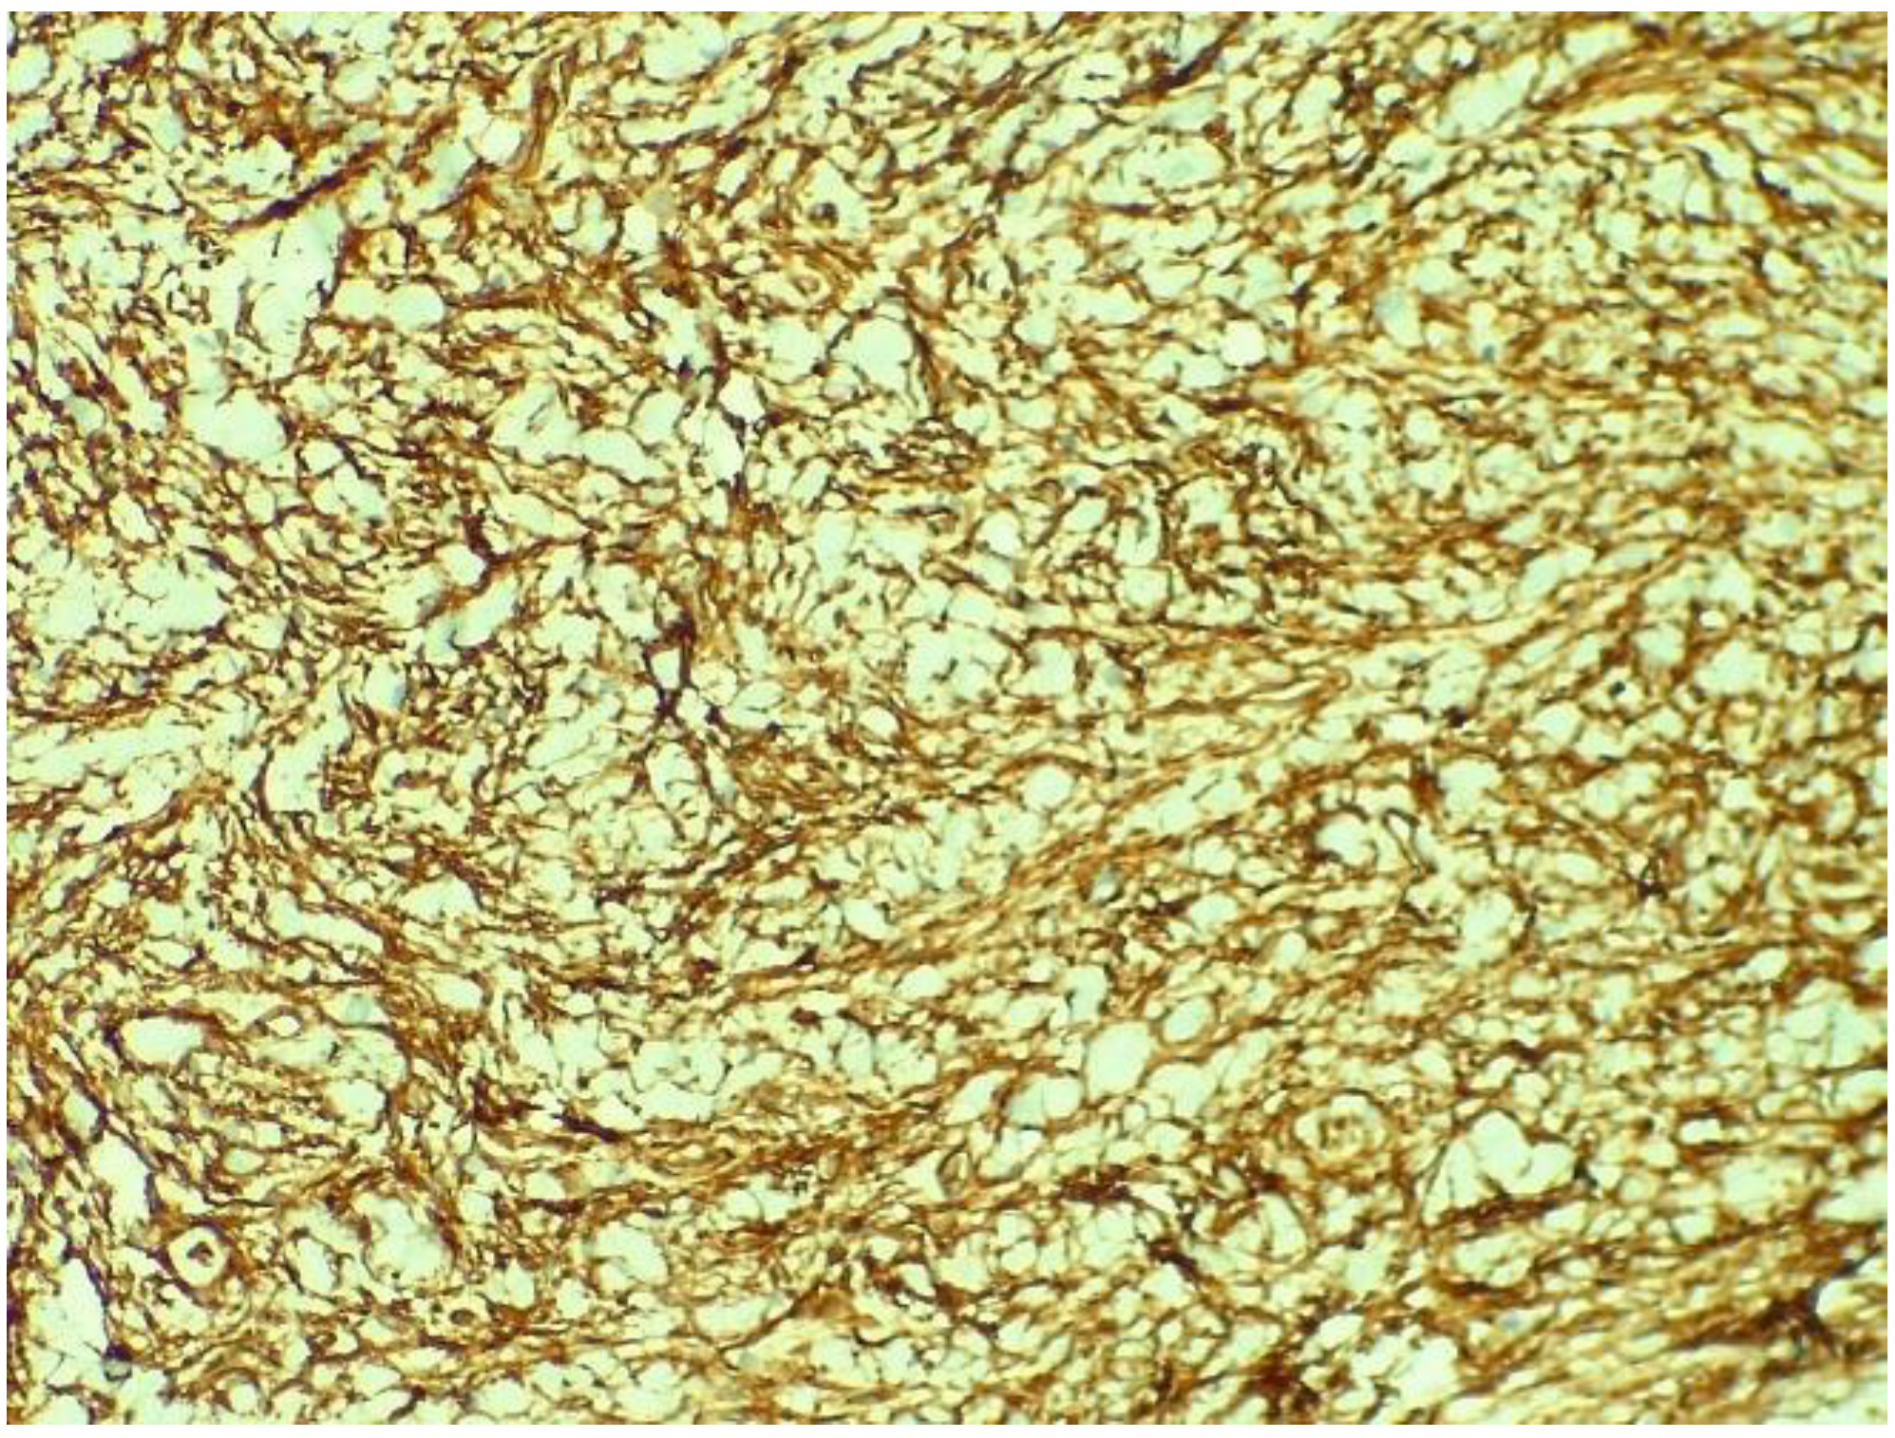

2. Case Report